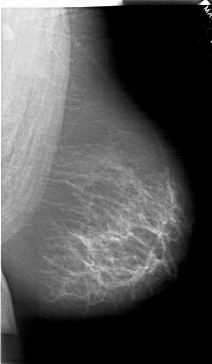

A_1518_1.LEFT_CC

LEFT_CC LINES 6871 PIXELS_PER_LINE 4126 BITS_PER_PIXEL 12 RESOLUTION 43.5 OVERLAY